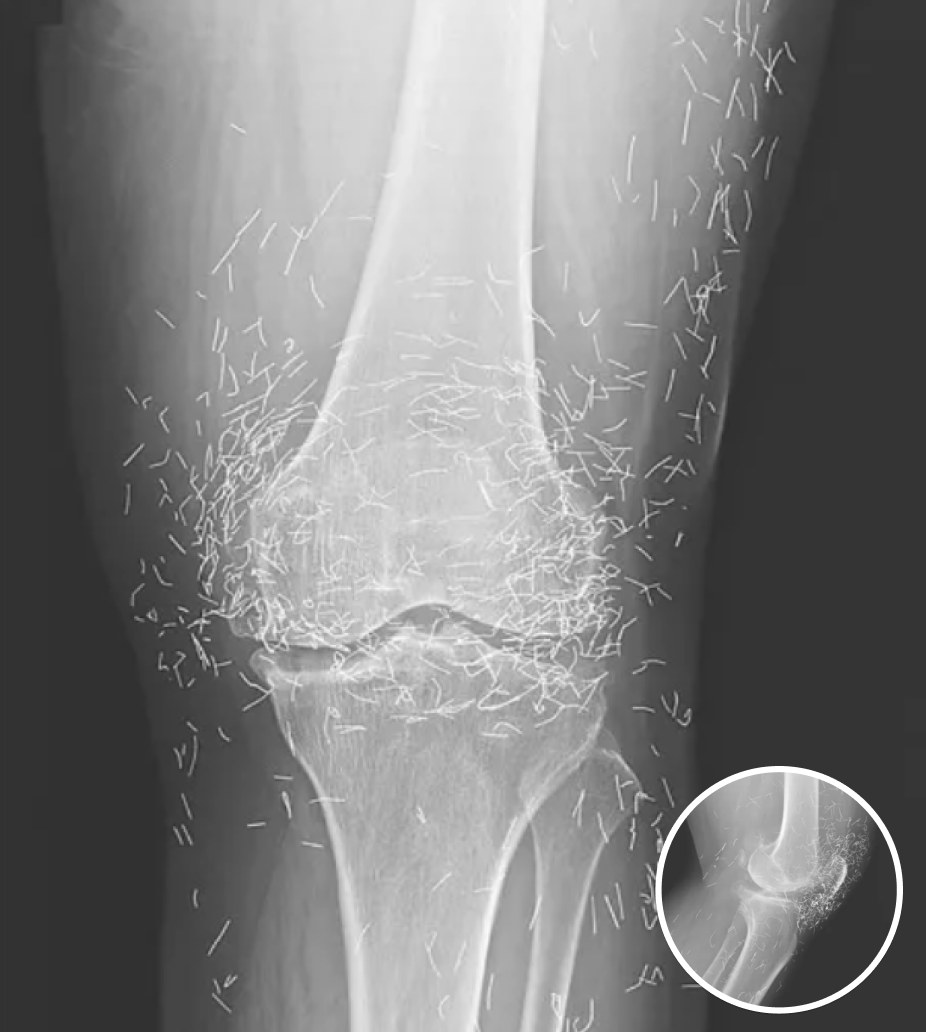

A X-ray of the patient’s knee showing acupuncture needles embedded in the tissue, Photo Credit: Reddit

A X-ray of the patient’s knee showing acupuncture needles embedded in the tissue,

A routine X-ray revealed an unexpected surprise when doctors examined the knees of a 65-year-old woman suffering from severe joint pain. What they found was nothing short of astonishing — hundreds of tiny gold needles embedded deep in her tissue.

There are other complications as well. Needles lodged in tissue can interfere with medical imaging. “They can obscure parts of the anatomy on an X-ray,” Guermazi noted. Even more alarming, patients with metal fragments in their bodies should never undergo an MRI, as the magnetic force could cause the needles to move — potentially puncturing blood vessels and causing life-threatening damage.